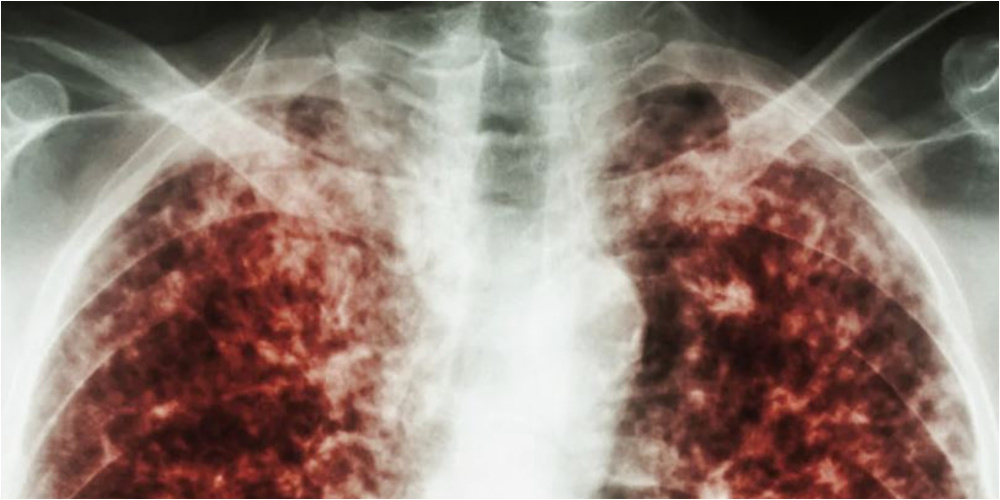

У учителя столичной школы выявлен туберкулез. Какие меры предприняты

После сообщения о заболевании педагога туберкулезом родители учеников школы №37 выразили обеспокоенность мерами реагирования. В санэпидслужбе заявили, что все контактные лица выявлены и обследуются.